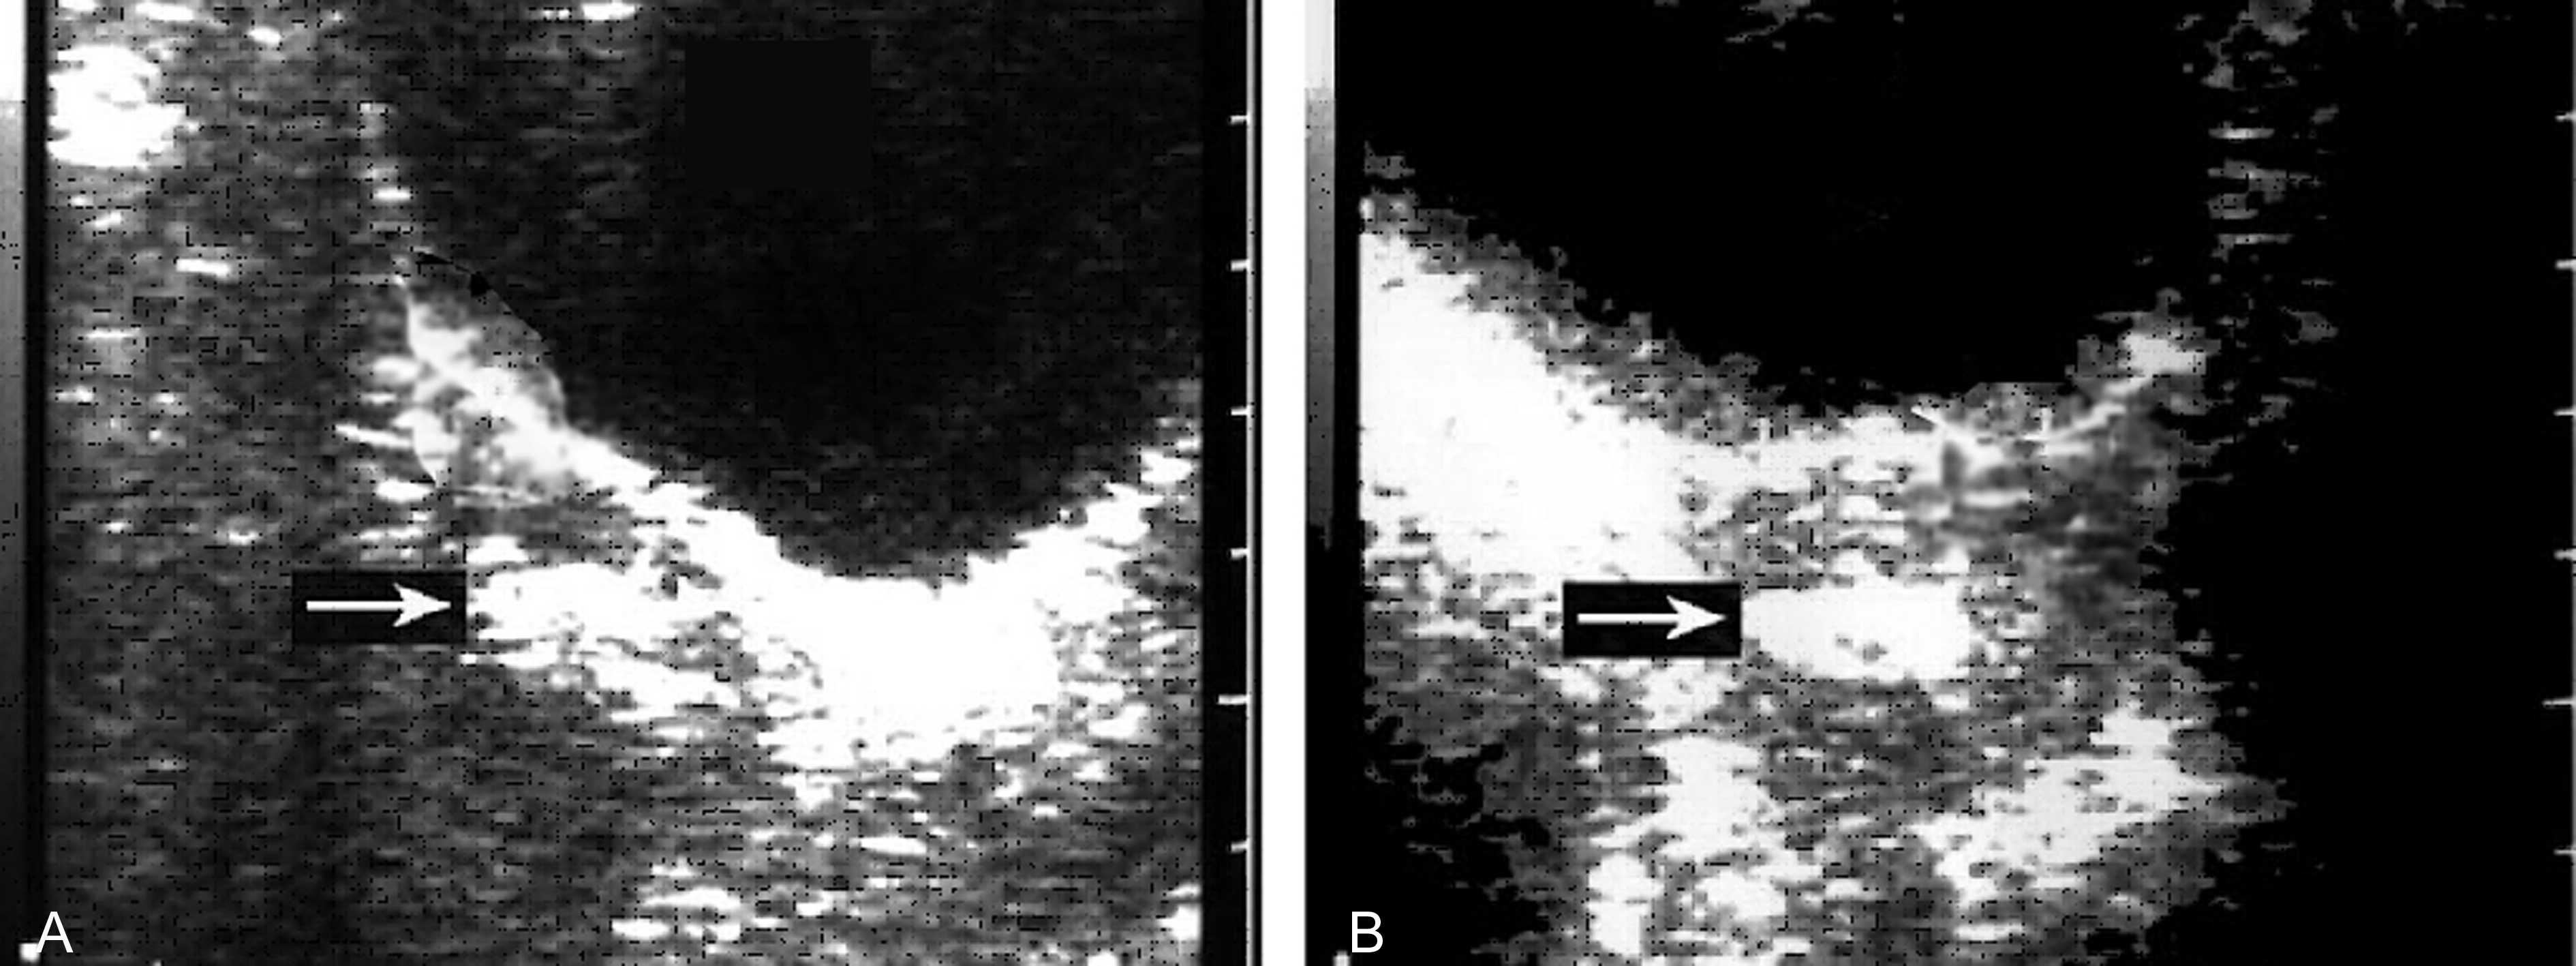

子宫小于停经月份,妊娠囊消失,宫腔内残存不规则无回声区或低回声区,分布不均匀(图4),或可见死亡的胚胎或胎儿回声,或可显示胎儿的骨骼强回声。结合病史可作出不全流产的诊断。

图4 不全流产声象图:胎体已排除,箭头指示宫腔内及宫颈管处仍有胚胎残留物

胎盘、绒毛组织等残留时显示为宫腔内较低而模糊的不规则回声区,随着时间的延长,其回声逐渐增强,边缘逐渐清晰,但回声仍不均匀。人工流产后妊娠产物的残留亦显示同样的回声。